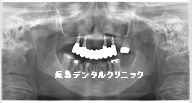

歯周病の上の歯をすべて抜歯しインプラントブリッジで治療した症例

またインプラントの数ですが

一般的には

上顎の場合は6~8本ですが

今回のように

顎の大きさが小さいので

4本のインプラントで

10本の被せ物を支えます。